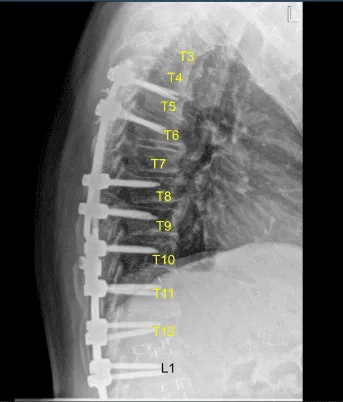

A new cobalt-chrome 5.5 mm Z-rod was selected, cut to proper size, connected to a domino side connector that was already in place across the tulips of the pedicle screws and secured with locking caps after some sort of bending was performed. All locking caps were final tightened with a torque and anti torque devices.

AP and lateral x-rays and final CT scan showed appropriate positioning of all the hardware. Morselized allograft with bone morphogenic protein was packed in lateral gutters on the left side for new fusion arthrodesis. Vancomycin powder was applied. Hemostasis was confirmed. A medium size Hemovac drain was tunneled in a subfascial manner and secured to the skin with a nylon suture.

Sagittal View of Thoracic spine postoperative X-ray